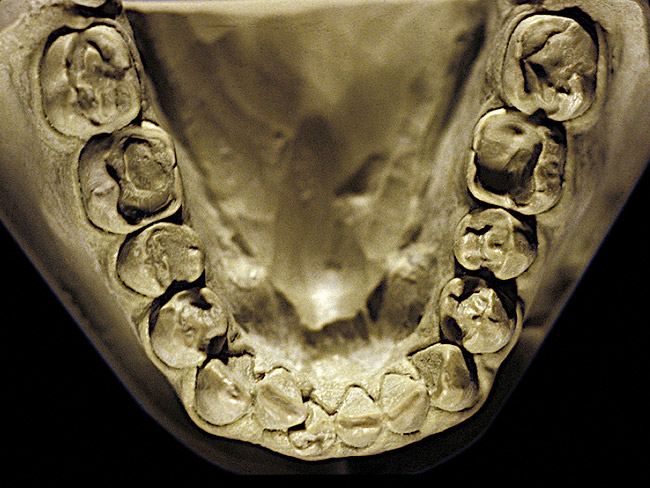

Figure 6  Moderate NCLTS from bruxism, mandibular arch.

The patient shown in Figure 3 and Figure 4 exhibited severe NCLTS from bruxism. Examination of the casts indicated that the NCLTS was progressively greater toward the anterior teeth. Cupping and cratering was not present because there was no secondary cause. Figure 5 and Figure 6 detail another bruxism patient, but to a lesser degree and one with cupping/cratering caused by toothpaste. The cups or craters were not caused from bruxism because the teeth could not touch the bottom of the invaginations. In both featured patients, upon hand-articulating the casts, the NCLTS facets matched up and the diagnosis of bruxism was confirmed.